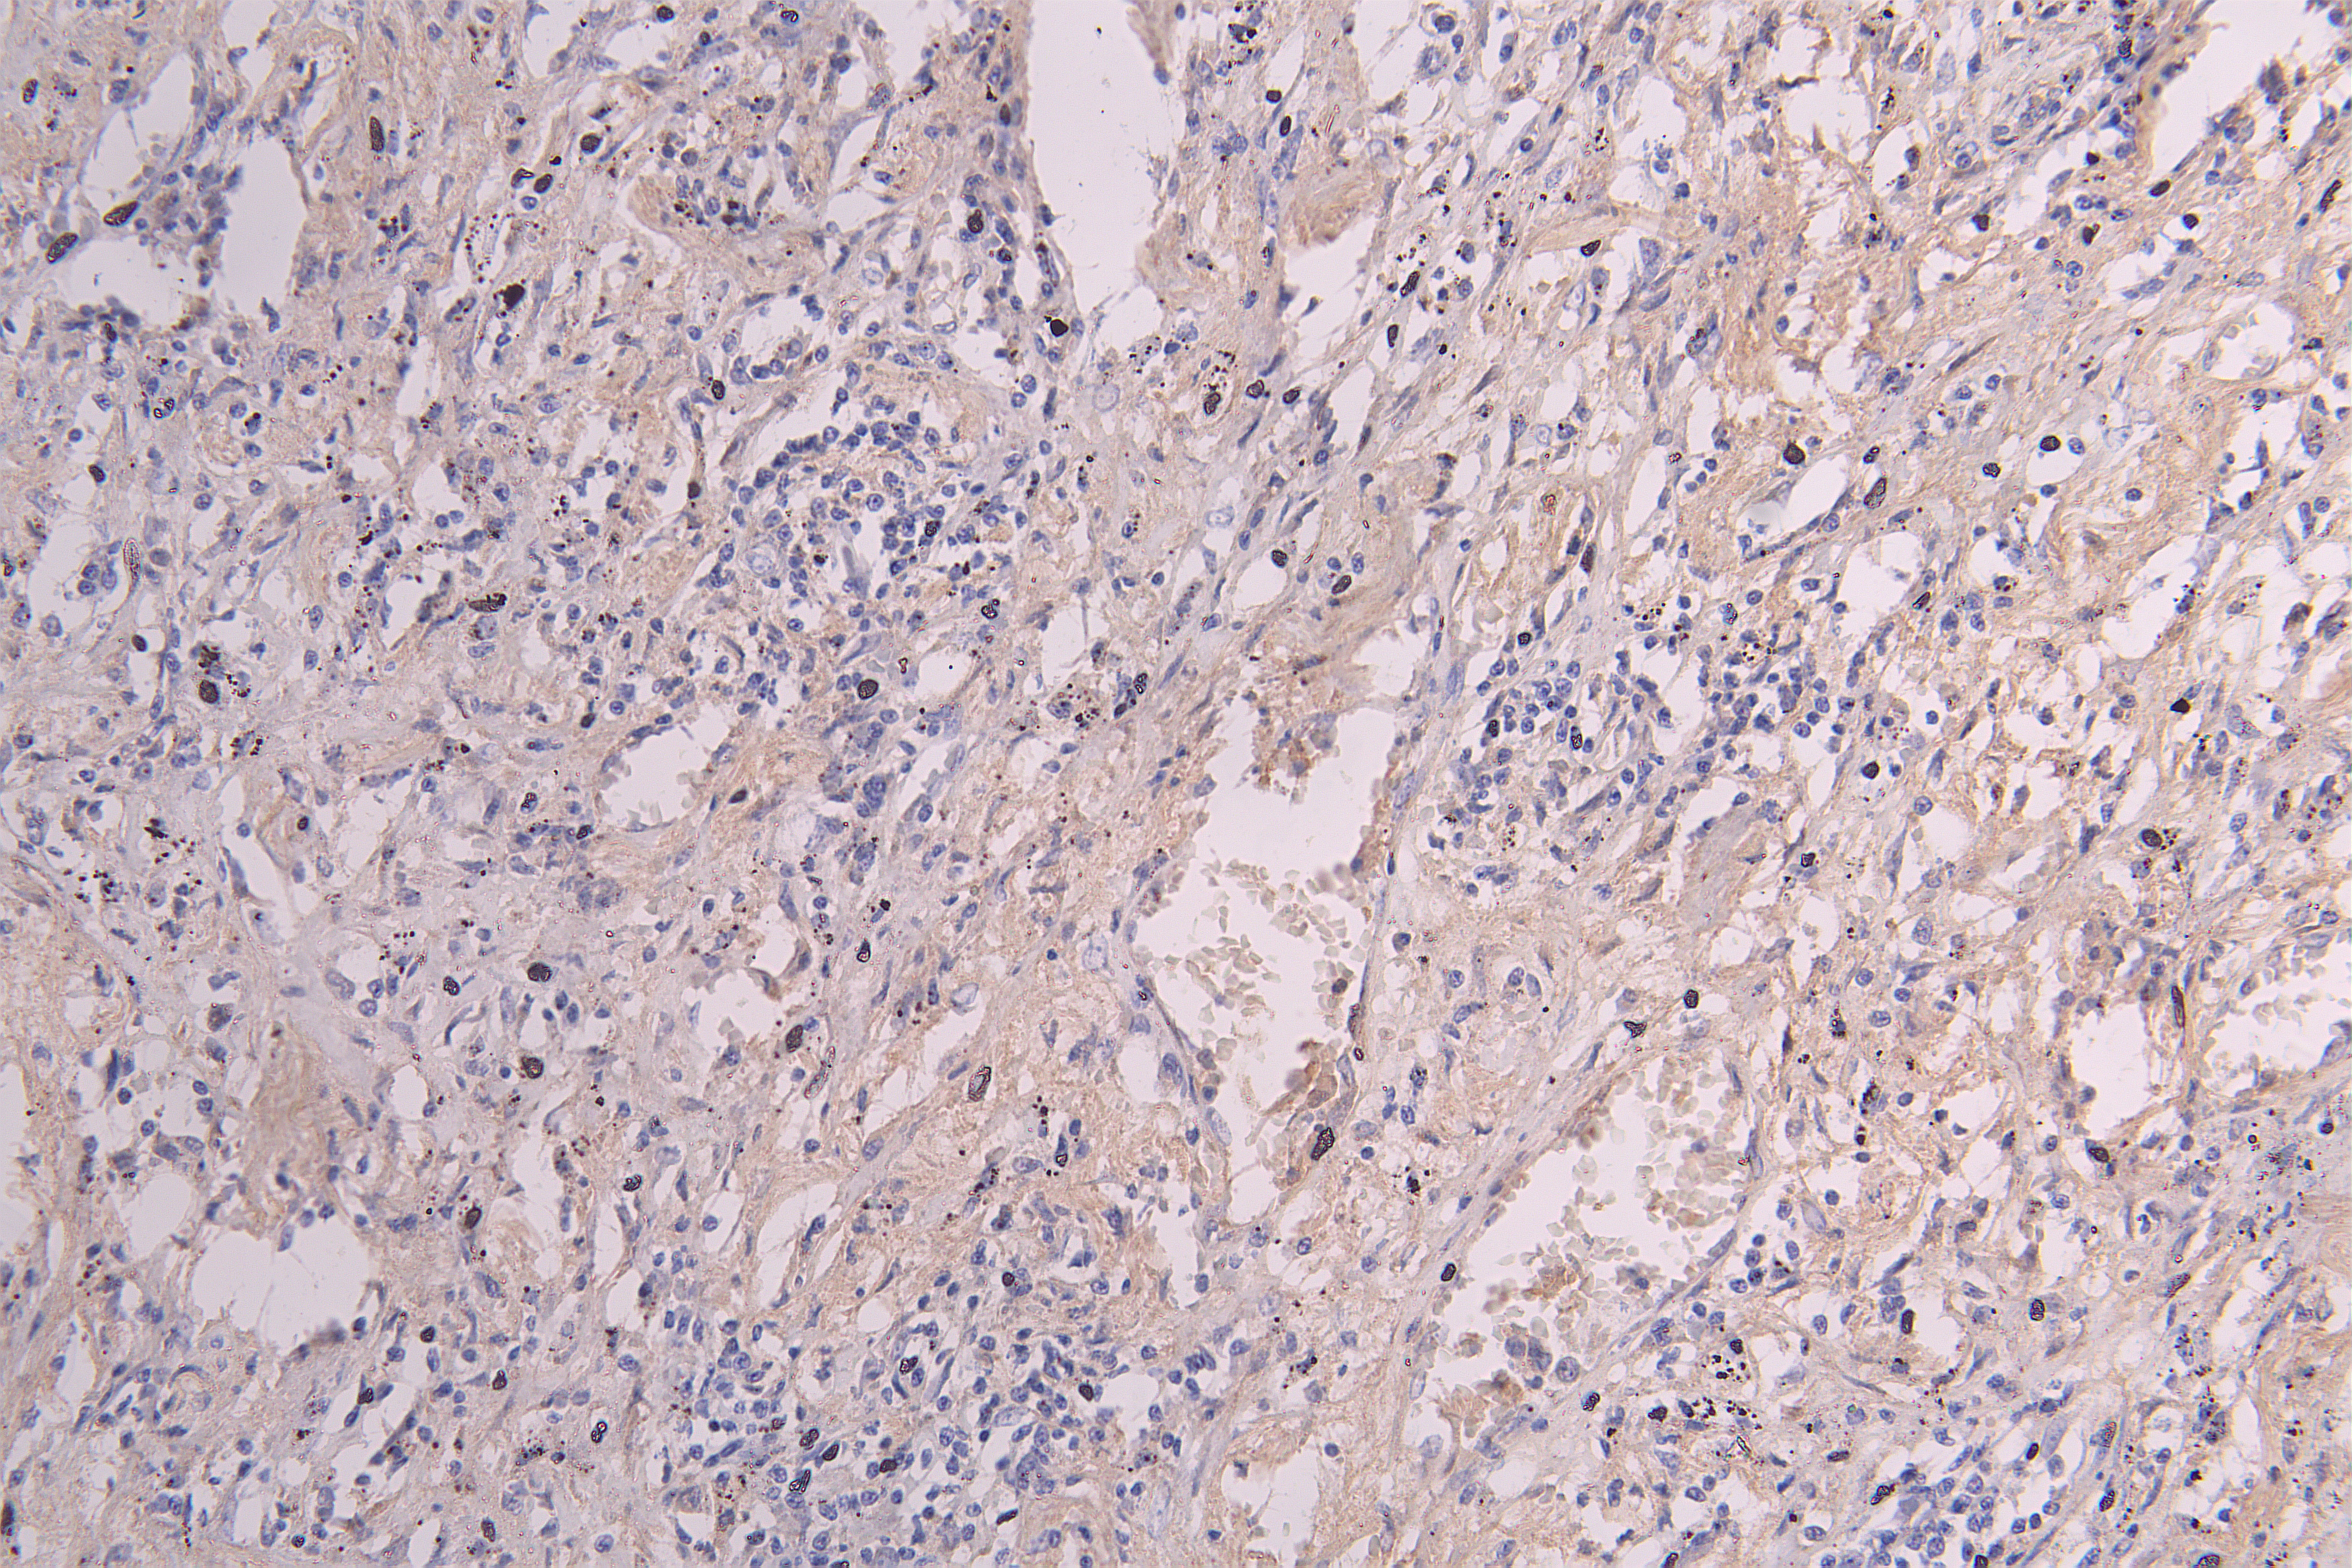

IHC image of CSB-RA011048MA1HU diluted at 1:300 and staining in paraffin-embedded human lung cancer performed on a Leica BondTM system. After dewaxing and hydration, antigen retrieval was mediated by high pressure in a citrate buffer (pH 6.0). Section was blocked with 10% normal goat serum 30min at RT. Then primary antibody (1% BSA) was incubated at 4°C overnight. The primary is detected by a Goat anti-Human IgG labeled by HRP and visualized using 0.05% DAB.